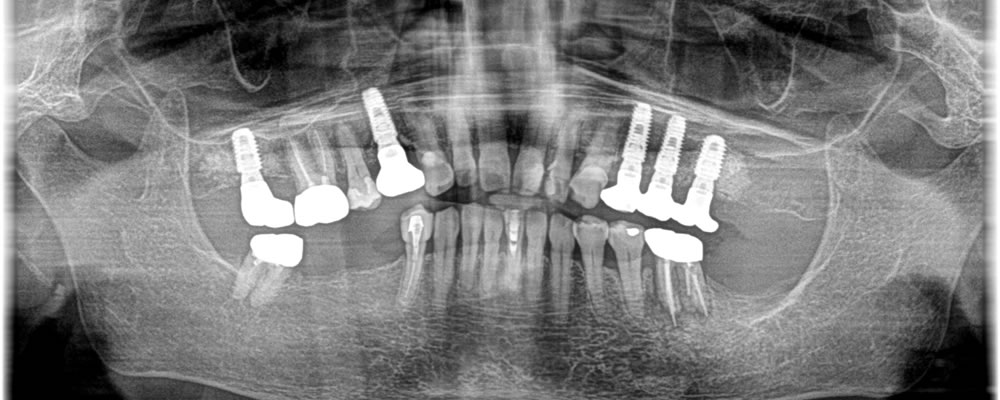

| 費用 | 右上7 インプラント大臼歯 407,000円(上部構造含む) 右上4 インプラント小臼歯 429,000円(上部構造含む) 左上4.5 インプラント小臼歯 429,000円×2(上部構造含む) 左上6 インプラント大臼歯 407,000円(上部構造含む) 骨造成 165,000円 |

感染により骨が大きく損失してしまっている部位には骨造成を同時に行い、なるべくインプラントの持ちが良くなるようにしました。治療後は今まで噛むことが出来なかった部位でしっかりと噛むことが出来るようになり、大変満足していただいております。

治療から3年が経った今でも、歯科衛生士の指導のもと定期的にクリーニングに通っていただいているため、治療直後と変わらずしっかりと噛むことができ、きれいな状態を保てています。

治療後のケアをしっかりとすることによりインプラントの持ちに大きく差が出るため、術後のケアは何よりも重要です。定期的なケアを行うことで何年経っても良い状態を保ち、インプラントを長く使っていただけるようにおすすめしています。